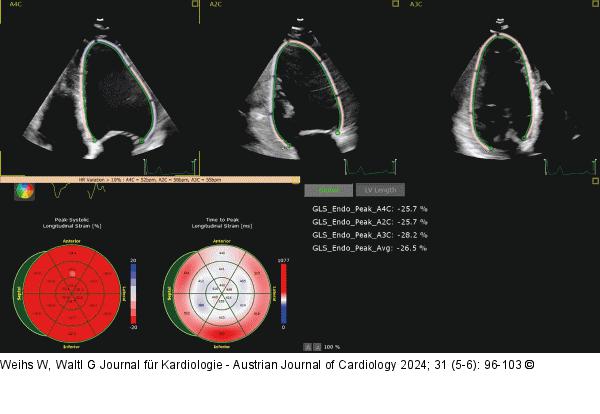

Abbildung 7: Echo Darstellung des globalen longitudinalen Strains (GLS) bei einem Normalbefund. |

Darstellung des globalen longitudinalen Strains (GLS) bei einem Normalbefund. |